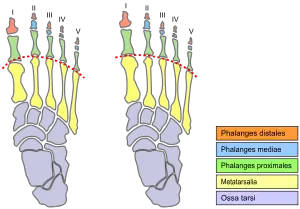

| Dorsal surface of a right foot with Morton's toe (left image) and without (right image). The dashed line highlights joint position. Metatarsals in yellow. | |

The distal metatarsal bones vary in relative length compared to the proximal. For most feet, a smooth curve can be traced through the joints at the bases of the toes (the metatarsal-phalangeal, or MTP, joints). But in Morton's foot, the line has to bend more sharply to go through the base of the big toe, as shown in the diagram. This is because the first metatarsal, behind the big toe, is short compared to the second metatarsal, next to it. The longer second metatarsal puts the MTP joint at the base of the second toe further forward.

If the big toe and the second toe are the same length (as measured from the MTP joint to the tip, including only the toe bones or phalanges), then the second toe will protrude farther than the big toe, as shown in the photo. If the second toe is shorter than the big toe, the big toe may still protrude the furthest, or there may be little difference, as shown in the X-ray.